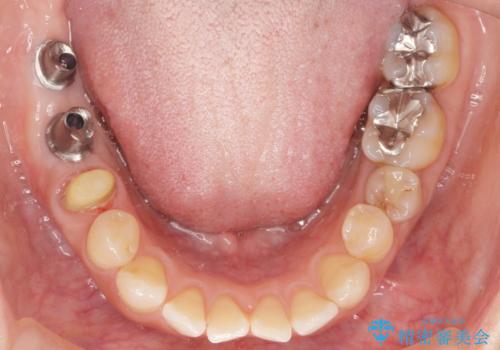

患者様のご希望により、右下大臼歯2本(右下76)のインプラント治療、右下小臼歯(右下5)の根管治療及び補綴治療を行いました。

割れていた歯の周囲組織の炎症が強く、骨の厚みが薄かったため、インプラント埋入時に骨増生(GBR)を行いました。

インプラントの種類:ストローマン BLT

クラウンの種類:ベレッツァクラウン(右下76)、ジルコニアクラウン スタンダード(右下5)